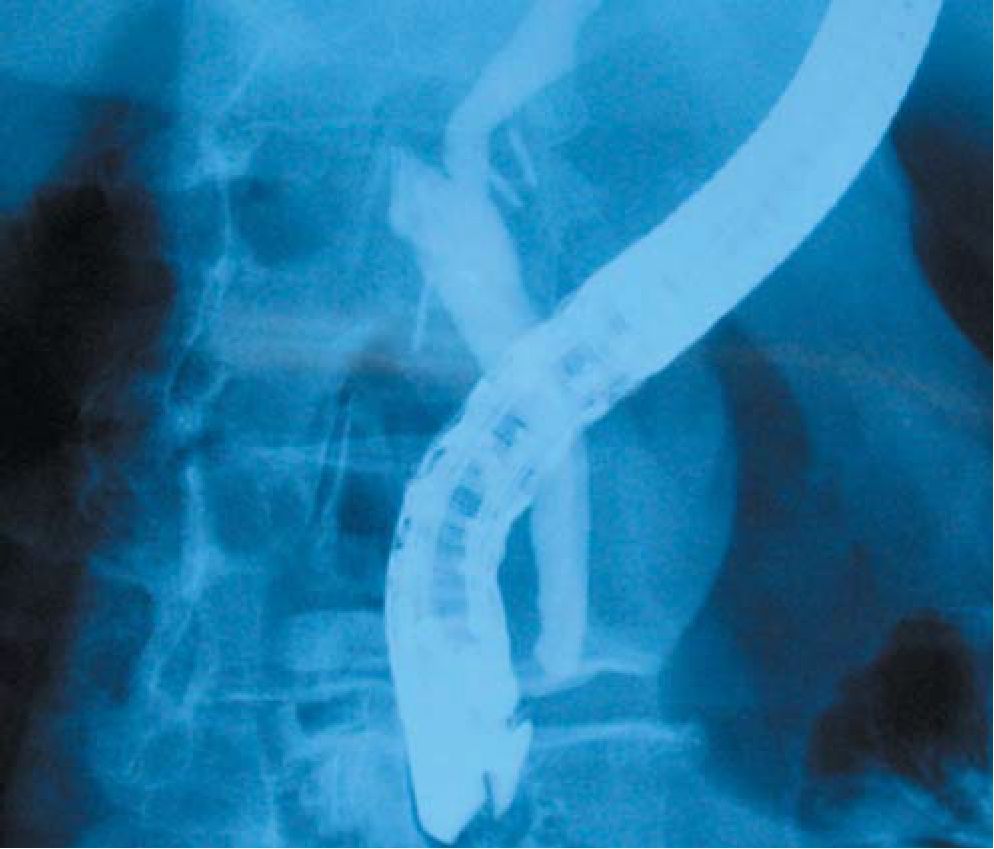

При наличии в анамнезе или в момент поступления у больного симптомов желтухи и холангита, а также при регистрируемом повышении уровня билирубина и трансаминаз, необходимо выполнить эндоскопическую ретроградную панкреатохолангиографию. Она дает информацию о характере желтухи, наличии конкрементов в гепатикохоледохе, особенностях анатомии желчных протоков, наличии холецистохоледохеального или билиодигестивного свищей (рис. 4).

Рис. 4. Разобщенный холедохо-толстокишечный свищ.

Соблюдение этих правил позволяет получить широкий (не менее 2 см), с хорошо адаптированными слизистыми анастомоз, не нуждающийся во временном или каркасном дренировании (рис. 5).

Рис. 5. Общий вид наложенного холедохо-еюно анастомоза на атключенной по Ру петле тощей кишки.